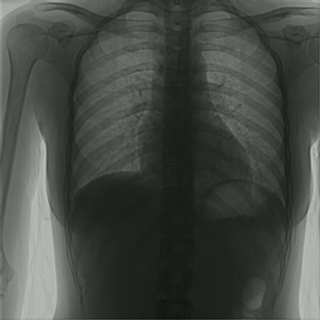

動(dòng)態(tài)DRF集數(shù)字化攝影、數(shù)字化透視、數(shù)字化造影等功能于一身,臨床應(yīng)用廣泛,還能在透視情況下進(jìn)行高清點(diǎn)片,這個(gè)功能對(duì)于老年人疾病的診斷更具意義,因?yàn)槔夏瓴⊥哂信R床癥狀及體征不典型,多病共存以及病情重,變化快等特點(diǎn)。動(dòng)態(tài)DR能在連續(xù)透視情況下觀察病灶,特別是在觀察老年人心肺功能方面能在發(fā)現(xiàn)病灶后快速點(diǎn)片,精準(zhǔn)獲取病灶部位高清圖像,更有利于醫(yī)生做出正確的診斷。

對(duì)于肢體損傷性患者的診斷,比如骨折患者,動(dòng)態(tài)DRF也有獨(dú)特的優(yōu)勢(shì):動(dòng)態(tài)大幅面透視圖像,便于觀察完整骨性胸廓、心、肺、膈肌在呼吸運(yùn)動(dòng)狀態(tài)下的整體狀態(tài),有利于識(shí)別肋骨骨折部位和位置,而且動(dòng)態(tài)DR可在透視下變換患者體位,使與組織器官重疊交叉或被遮蓋的肋骨得以清晰的顯示,在轉(zhuǎn)體過程中發(fā)現(xiàn)疑似病灶進(jìn)行實(shí)時(shí)毫秒級(jí)抓拍,對(duì)于隱匿性骨折的診斷優(yōu)勢(shì)明顯。